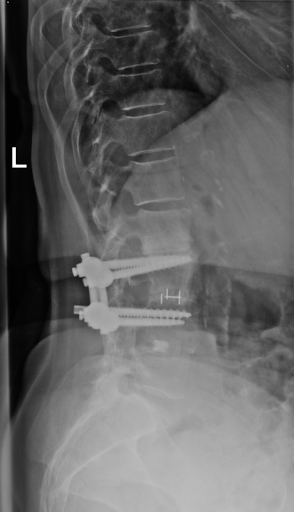

I enjoy the 3D Spine Simulator. This review helpful to know about spine.